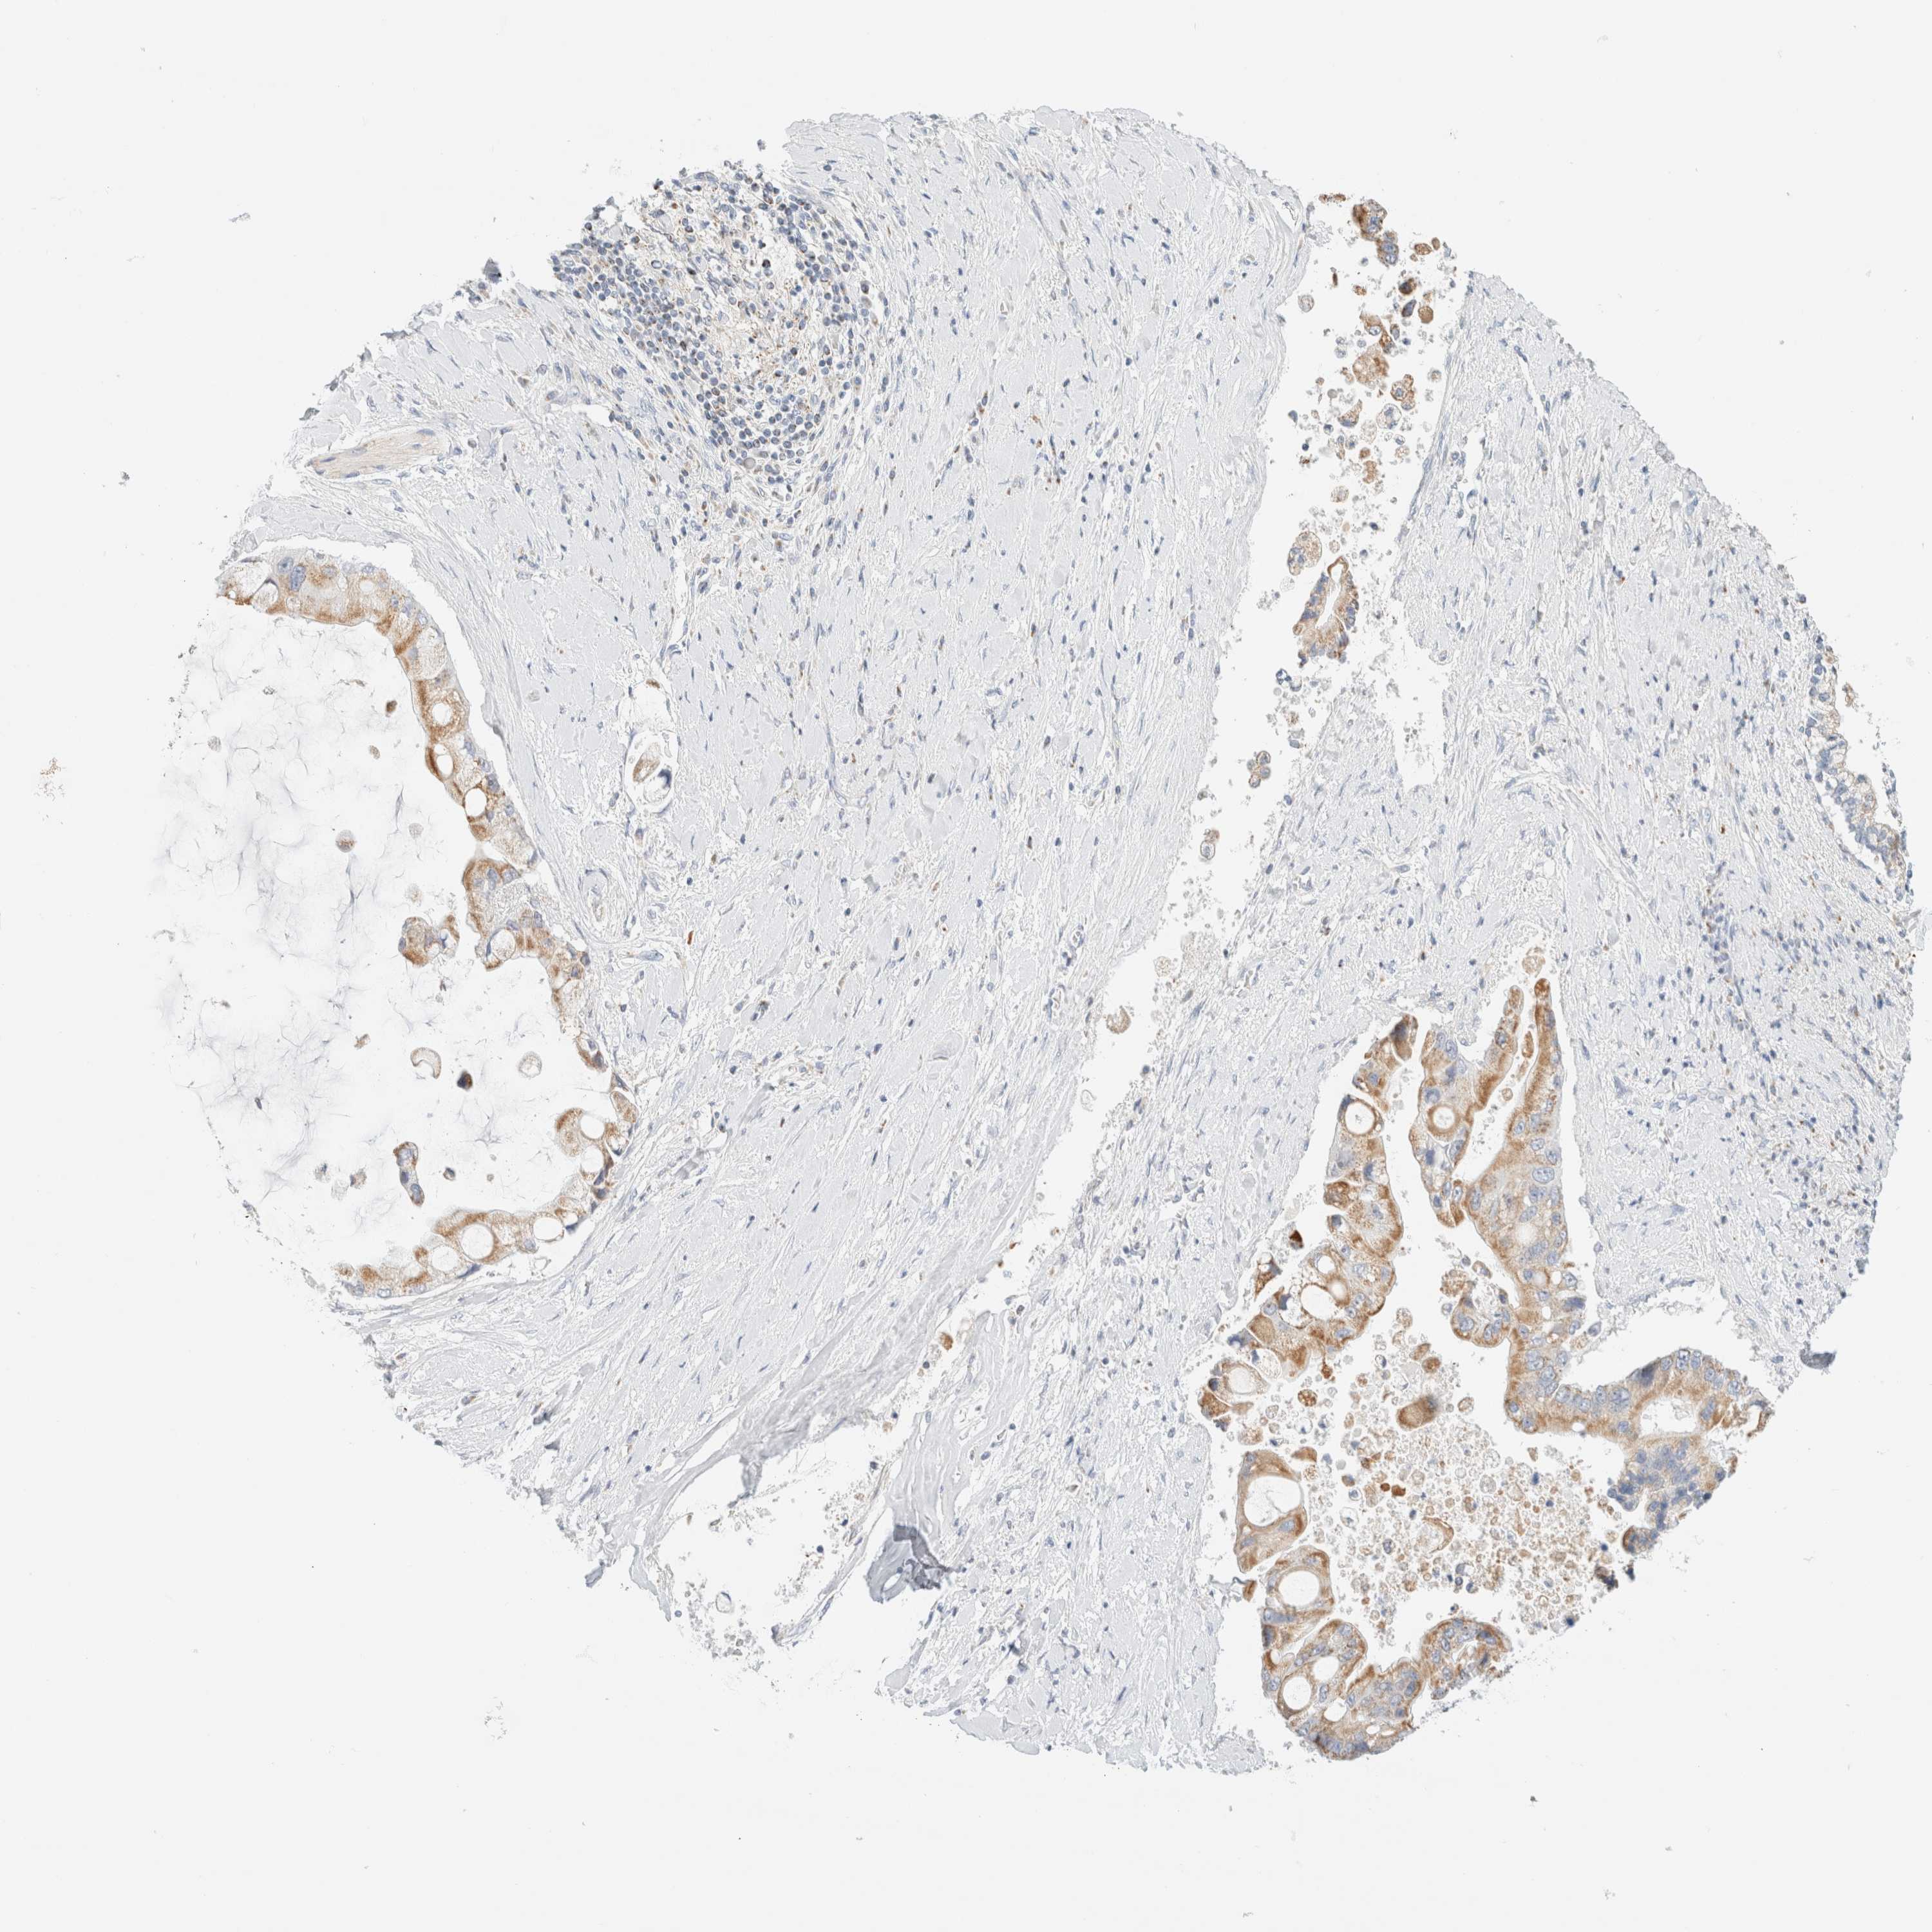

LIVER CANCER - Protein expressioni

A mouse-over function shows sample information and annotation data. Click on an image to view it in a full screen mode. Samples can be filtered based on level of antibody staining by selecting one or several of the following categories: high, medium, low and not detected. The assay and annotation is described here.

Note that samples used for immunohistochemistry by the Human Protein Atlas do not correspond to samples in the TCGA dataset.

Antibody stainingi

Antibody staining in the annotated cell types in the current human tissue is reported as not detected, low, medium, or high, based on conventional immunohistochemistry profiling in selected tissues. This score is based on the combination of the staining intensity and fraction of stained cells.

Each image is clickable and will lead to virtual microscopy that enables deeper exploration of all samples and also displays staining intensity scores, fraction scores and subcellular localization as well as patient and tissue information for each sample.

Antibody HPA020427

Antibody HPA024158

Antibody HPA024585

Staining

High

Medium

Low

Not detected

Intensity

Strong

Moderate

Weak

Negative

Quantity

>75%

75%-25%

<25%

None

Location

Nuclear

Cytoplasmic/membranous

Cytoplasmic/membranous,nuclear

Cholangiocarcinoma

Carcinoma, Hepatocellular, NOS